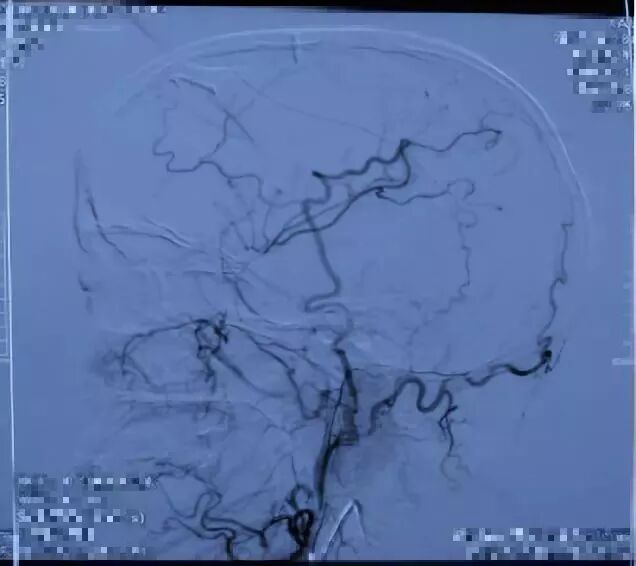

术中造影

术后一周复查CTA 提示吻合口通畅

术后半年(10月)入院复查DSA,示吻合口通畅,并行左侧脑血管重建术(STA-MCA吻合+颞肌贴敷术)